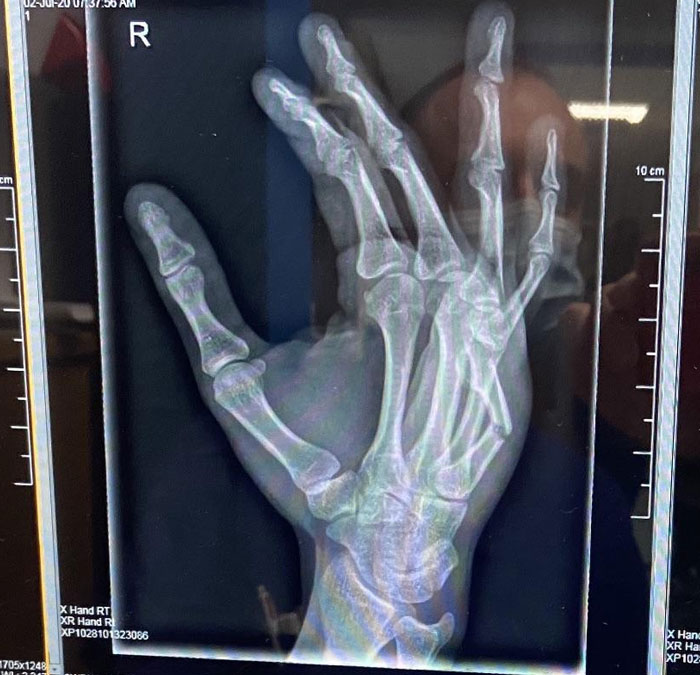

X-Ray Of A Panda Hand vs. A Human Hand; Pandas Have An Extra "Thumb" To Help Grip Bamboo Stalks